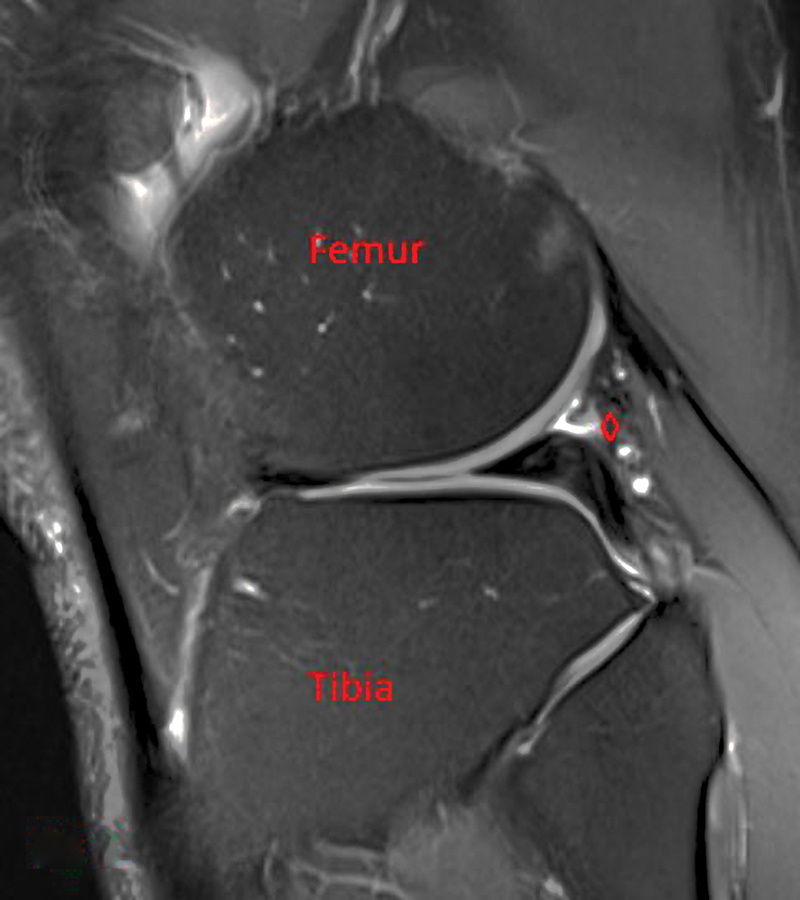

This case involves a healthy male with painful lateral knee pain and snapping after a hyperextension injury. Initially, this was felt to be from a displaced lateral meniscus tear; however, he failed to improve after meniscal debridement. Further workup with an ultrasound and magnetic resonance imaging identified an aberrant biceps femoris anatomy. He was taken to the operating room and the aberrant slip was identified. A tenodesis of the aberrant slip to the biceps femoris was completed. This resolved the patient's pain and snapping, and he was able to return to all activities.

Abstract Image